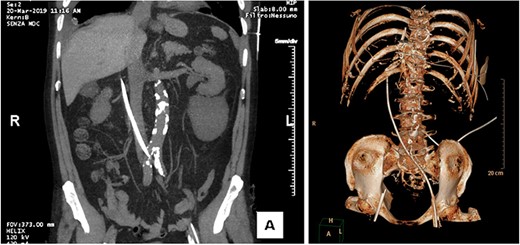

CT performed in urgency after catheter introduction shows the probe at the right side of the L2–L3 vertebral bodies, with the tip lying next to the portal vein.

Fluids and vasopressors (bolus of 500 ml of crystalloids, norepinephrine 0.1 mcg/kg/h) were administered to restore hemodynamic stability. Simultaneously, an abdominal FAST exam was performed with no evidence of intraperitoneal or pericardial free fluid, even if the location of the tip was unclear. Since the patient was hemodinamically stable, he was transferred for a thoraco-abdominal CT scan. Before, the decapolar electrode catheter was removed with concomitant administration of 3-factor prothrombin complex concentrate (1000 UI). As the patient was allergic to iodine, no contrast was injected. The CT scan revealed the distal part of the probe outside the IVC, at the L2–L3 vertebral level, and the tip free within the retroperitoneal space, near the portal vein, in absence of free fluid (Figure 1 a,b).